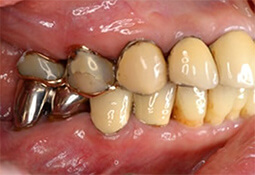

インプラント治療の症例

インプラント治療例その1(下顎奥歯にインプラント3本埋入、60歳代女性)

この症例のようにインプラント周囲炎を予防する為には審美性より清掃性、機能性優先をお勧めします。

| 治療内容 | インプラント治療(下顎奥歯にインプラント3本埋入) |

|---|---|

| 治療期間・回数 | 約3ケ月、約4~5回 |

| 治療費用 | ¥1,243,000 |

| 治療のデメリット | 歯に比べ感染に弱いので、徹底した口腔衛生管理が必須 保険適用外のため、自費診療となる |